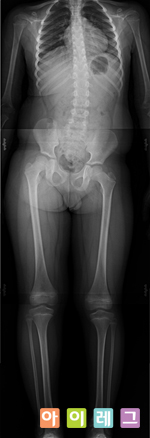

발, 다리의 문제(평발, 안짱다리, O다리, X다리, 다리길이

차이 등)가 원인이 되는 경우가 많습니다. 인간은 서 있거나

보행을 할 때 직립자세를 취하게 되기 때문에 발은 몸에서 가장

기초를 이루는

구조물입니다.

건물의 기초가 부실하면 균형이 무너지고 결국 오래 버티지 못하게

기울어지게 되는 것처럼 발에

문제가 있을 경우 무릎, 고관절, 심지어 척추에 까지 영향을

미칠 수 있습니다.

환자가 평발이나 안짱다리인 경우 전신 X-ray를 촬영하여 골반은

틀어지지 않았는지 척추측만증은 없는지 살펴보는 이유가 여기에

있습니다. 실제로 임상을 하면서 발, 다리에 문제가 있는 아이들은

어린나이에도 불구하고 잘못된 자세와 합쳐져 척추측만증이 있는

경우를 보게 됩니다.